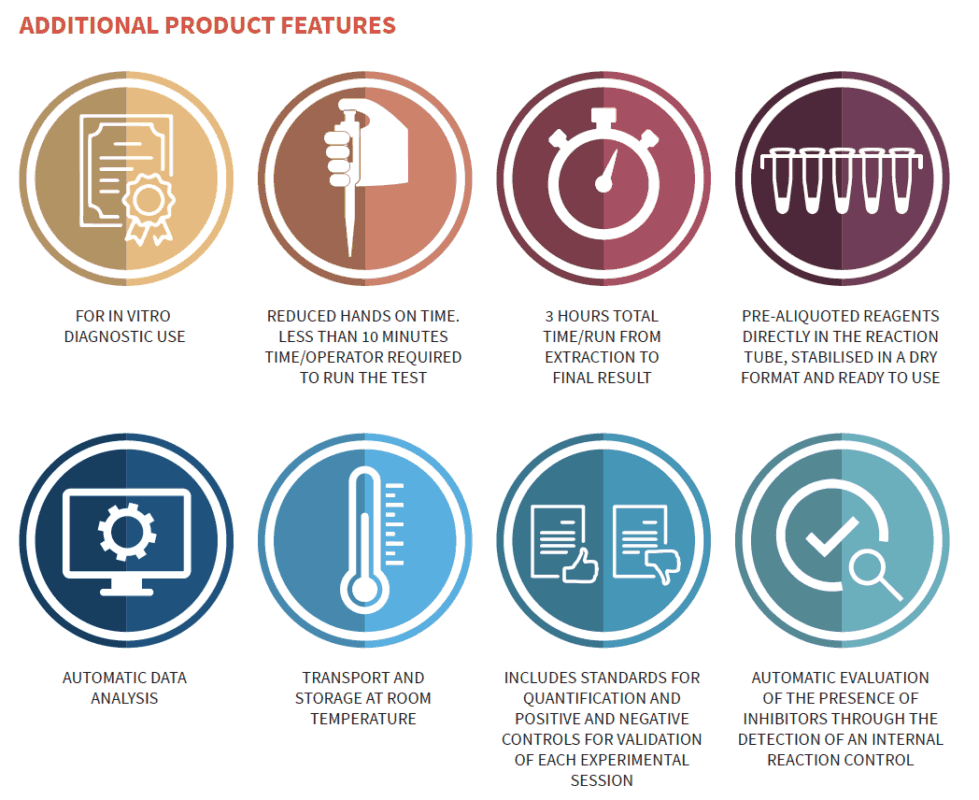

We would like to introduce the first and only kit that supports the early diagnosis of Colorectal Cancer (CRC). A non invasive test with a turnaround time from tissue to result is less than 3 hours with only 10 minutes of hands-on-time.

The Diatech EasyPGX ready FL-DNA (cod. RT029) kit is the first and only available kit for in vitro diagnostic use which allows the quantitative determination of DNA fragments with dimensions > 200bp present in the faeces. The quantitative analysis of DNA extracted from faeces in association with FOB test, represents a useful tool to improve early diagnosis of CRC by estimating the probability of CRC presence.